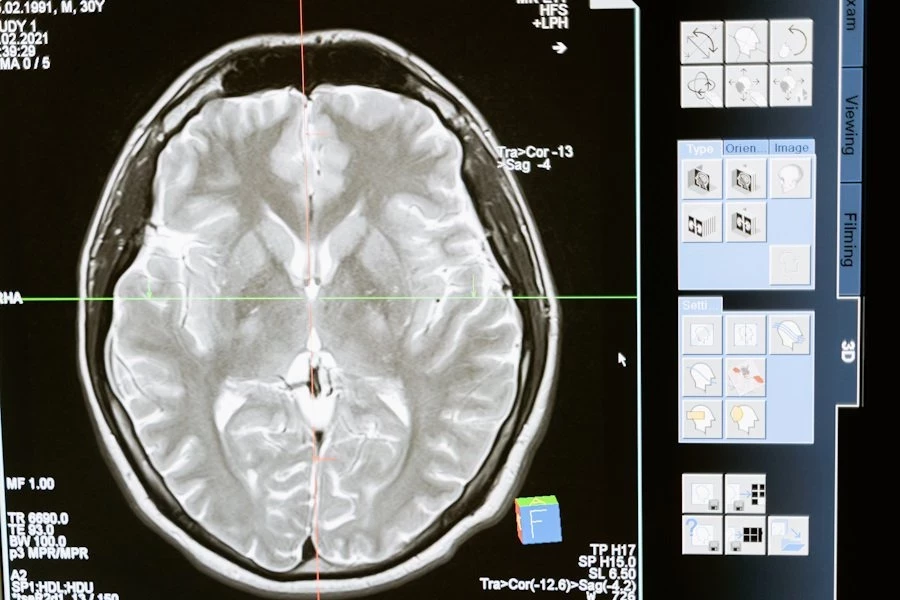

Фото из открытых источников

Ученые УрФУ синтезировали новое вещество с противоопухолевыми свойствами, которое может стать основой препарата для лечения глиобластомы — одной из самых агрессивных форм рака центральной нервной системы. Ожидается, что лекарство на его основе будет менее токсичным для пациентов по сравнению с существующими аналогами. Подробности исследования опубликованы на портале BioMetals, сообщает РИА Новости.

Глиобластома является наиболее распространенной злокачественной первичной опухолью головного мозга. Она чаще всего поражает лобные, височные, теменные и затылочные доли мозга и встречается преимущественно у людей старше 64 лет, причем мужчины страдают от этого заболевания чаще, чем женщины, отмечают ученые УрФУ.